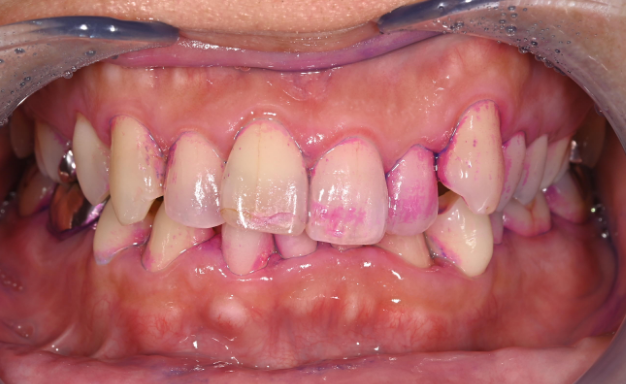

数値で管理する「見える予防」

• 歯周ポケット検査(歯と歯ぐきの間の溝の深さ)

• BOP(歯周ポケットを検査する際に出血があるかどうか)

歯周ポケットは「歯周病の進行度」を示し、BOPは「歯ぐきの炎症の程度(活動性)」を示す重要な指標です。特にBOPが高い状態は「歯周病・虫歯の進行リスクが高い状態」を意味します。

当院ではBOP10%以下にコントロールすることを一つの目標とし、状態の変化を継続的に評価していきます。

必要に応じてPCR(プラーク付着率)も測定し、より精密な管理を行います。

初診時

1ヶ月後

3ヶ月後